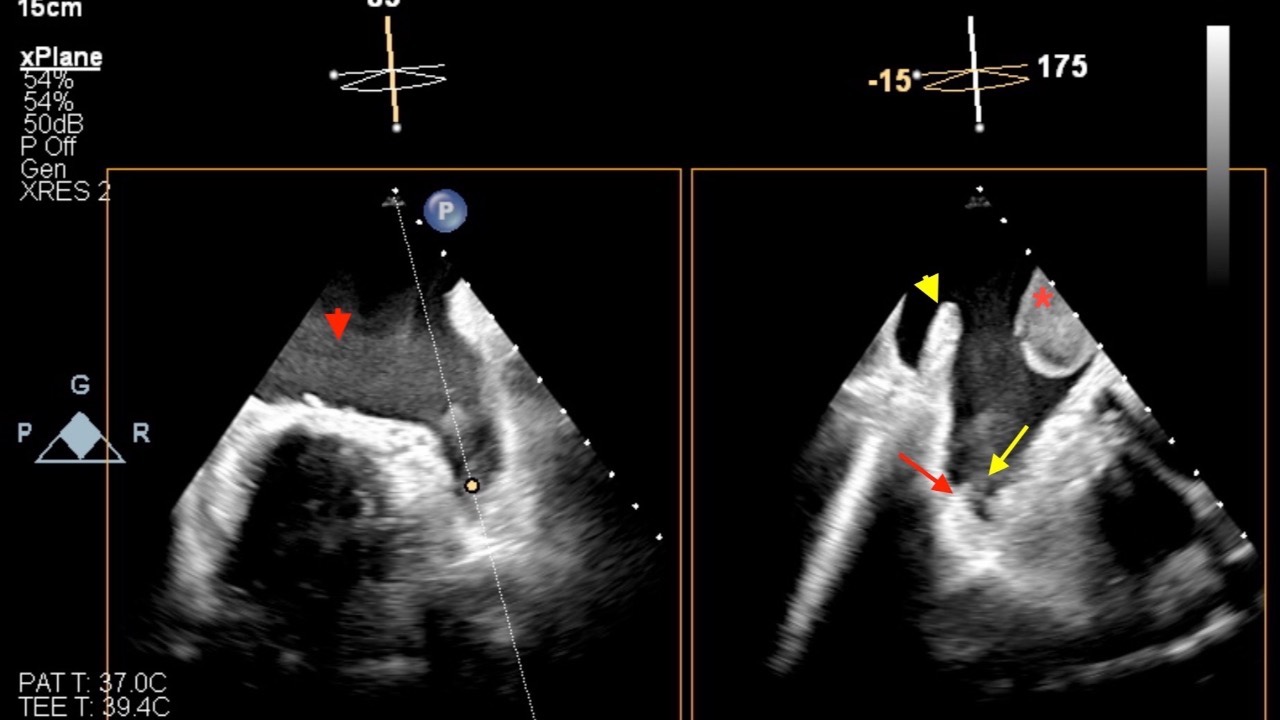

Atrial Fibrillation & Glaucoma

What do you tell your patients?...

A recent case control study looking at rates of glaucomatous visual field progression before and after the onset of atrial fibrillation found important outcomes for us to consider.

Longitudinal results and meta-analyses found a significant change in visual fiel...